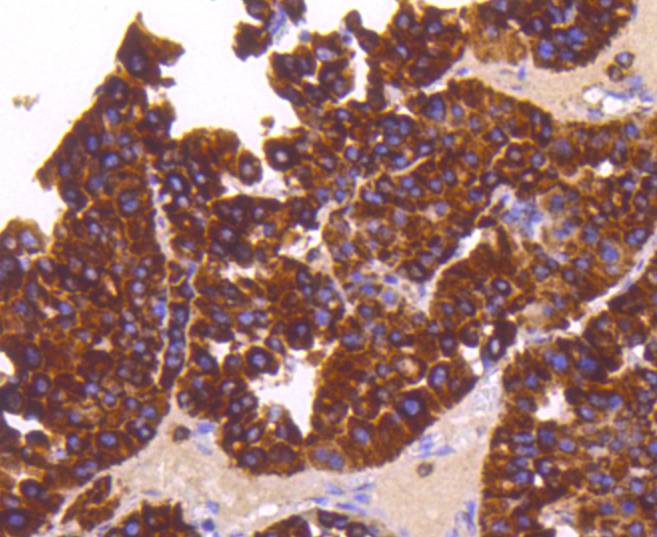

Immunohistochemical analysis of paraffin-embedded human liver cancer tissue using anti-Sonic Hedgehog Protein antibody. Counter stained with hematoxylin.